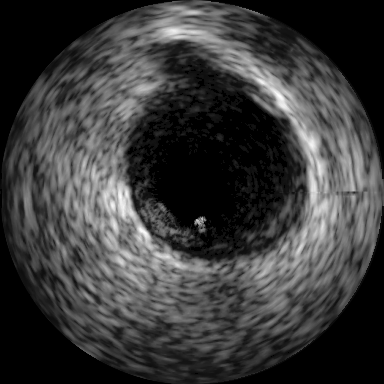

Intravascular Ultrasound Segmentation: We have used IVUS data from the 2011 MICCAI workshop [8] which is composed of pullbacks of different patients acquired at MHz (Dataset B). The proposed method is compared with nine different methods, where eight approaches have been reported earlier in [10]. In Table 1, we have included only the best results among the participants (P1-P8) in [8]. Subsequently 2D visualization of segmented IVUS contours are presented in Fig. 3(d) - (g) and the lumen and external elastic luminae border segmentation in the whole pullback is visualized111Supplementary material. The proposed method outperforms the recent related prior art [11] as presented in Table 1.